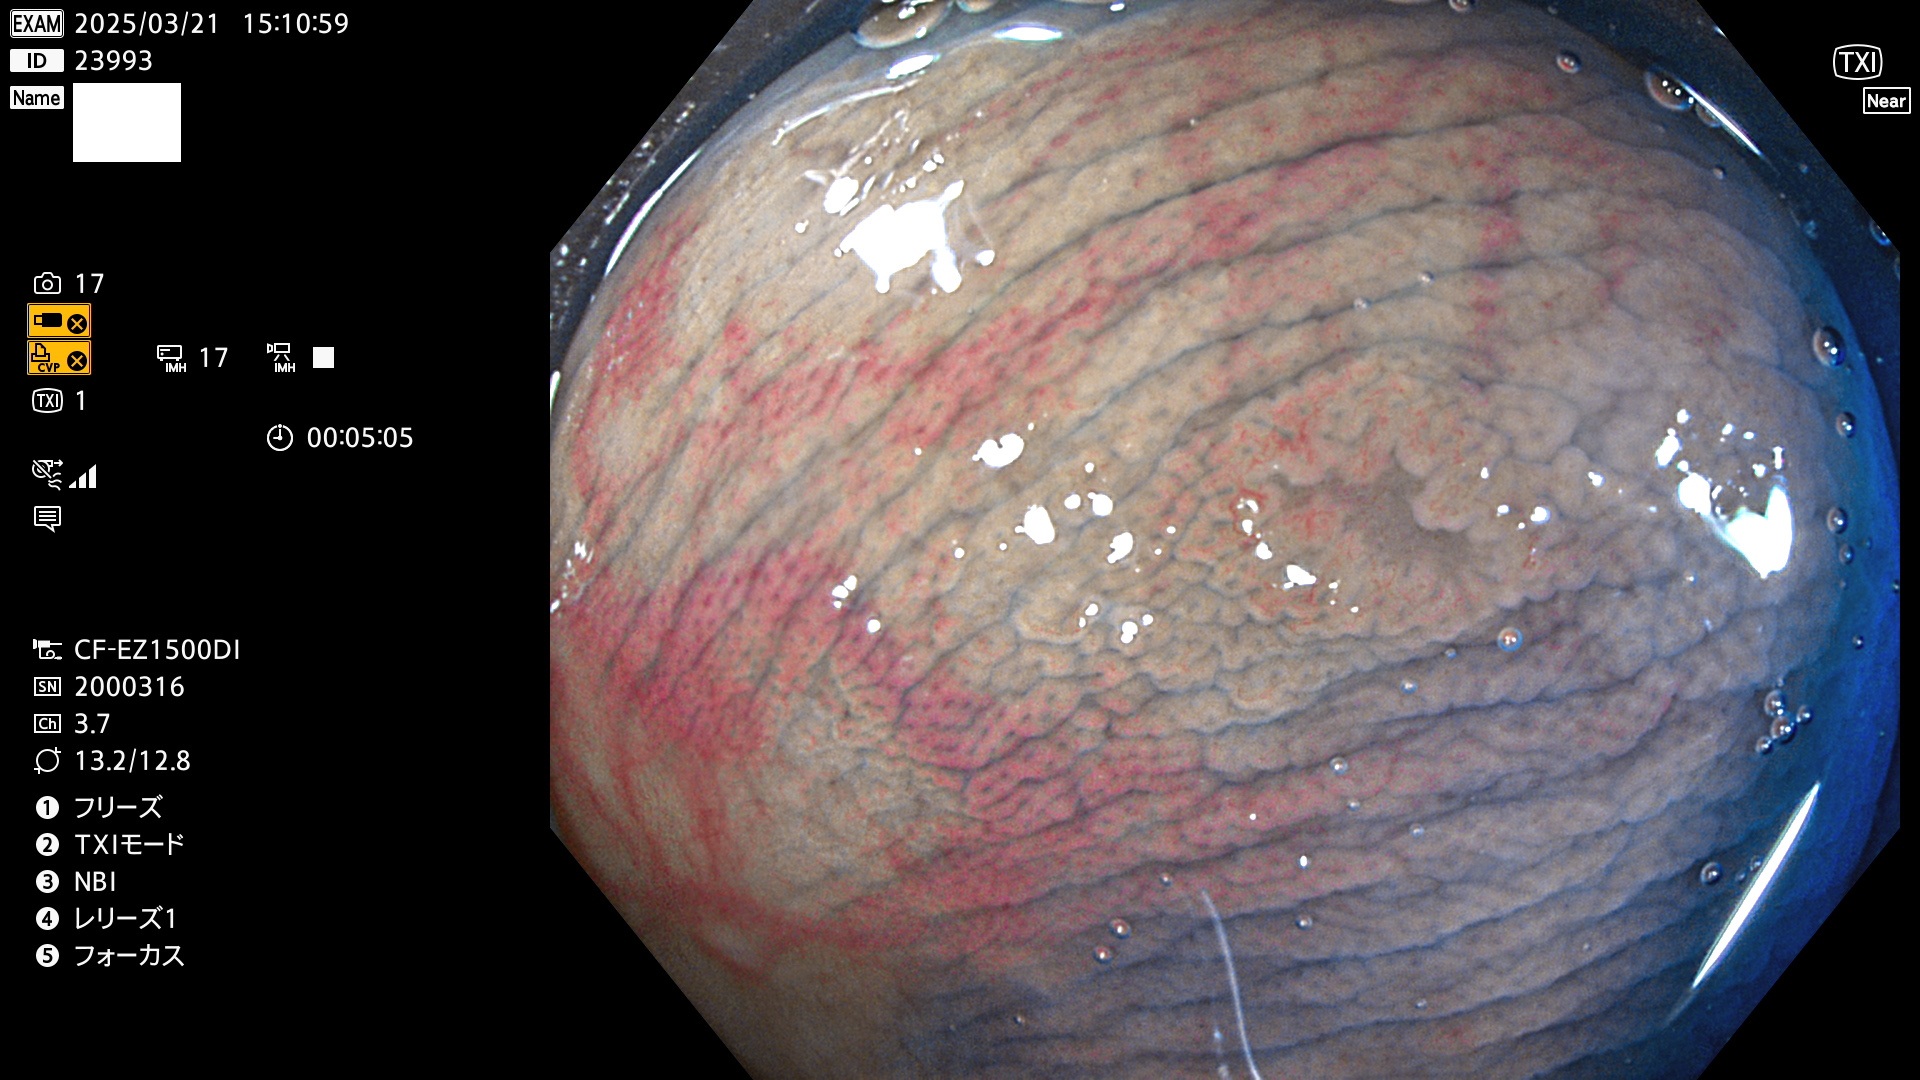

今週のUb、Uc型腺腫

完全に平坦な物をUb、陥凹している物をUcと呼びます。Ubは認識が困難で、Ucはびらん(炎症)と紛らわしいために見落とされやすく、「内視鏡後・大腸癌」の原因になります。

毎週の検査(木・金・土・日)に発見されたUb、Uc型・腺腫を、その週の日曜の夜にUPし1週間、提示します。

抽出の対象期間 2025年3月20日〜3月23日の4日間(48件の検査)10個 (10/48=21%)